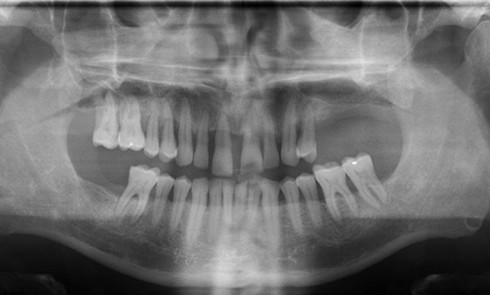

Article réservé à nos abonnés Planification et gestion de la phase provisoire d’une patiente atteinte d’usure érosive

Coordination : Kinz Bayet Situation clinique initiale et synthèse diagnostique Une patiente, âgée de 30 ans, se présente en consultation pour...